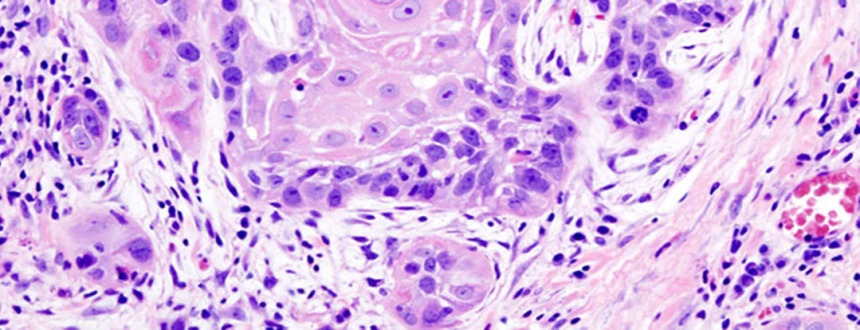

Большинство раковых заболеваний головы и шеи представляют собой плоскоклеточные карциномы. Этот вид онкологии начинается в клетках эпителия, который составляет тонкий слой поверхностной ткани. Непосредственно под эпителием, на некоторых участках головы и шеи имеется слой влажной ткани, называемый слизистой оболочкой. Если рак обнаружен только в плоскоклеточном слое, он называется карциномой in situ. Если рак разросся за пределы этого клеточного слоя и перешел в более глубокие ткани, он называется инвазивным плоскоклеточным раком.

Если рак головы и шеи начинается в слюнных железах, опухоль обычно классифицируется как аденокарцинома, аденоидная кистозная карцинома или мукоэпидермоидная карцинома.